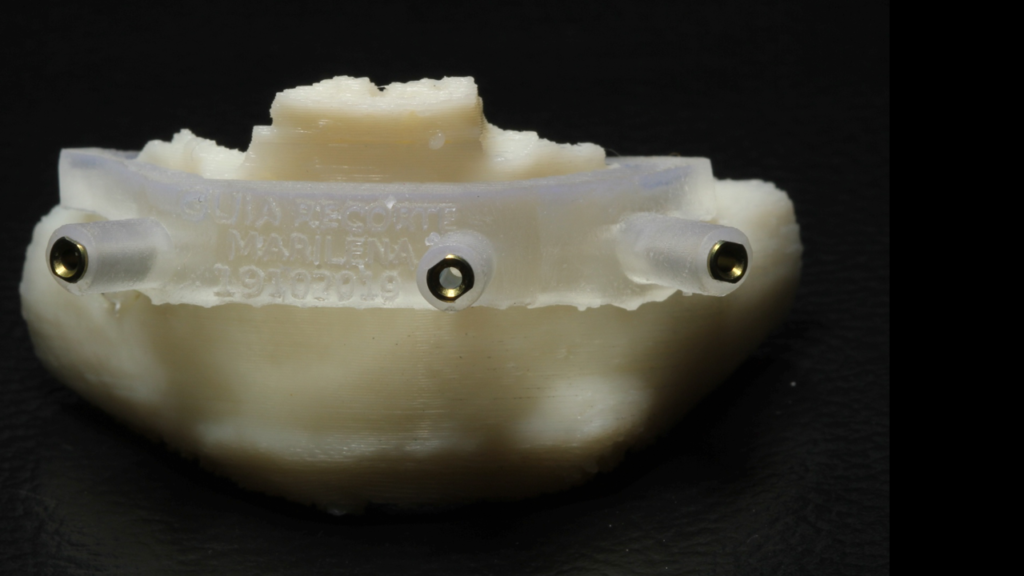

Através do programa Blue Sky (em parceria com a empresa Odontoplanning), foi feito planejamento guiado com 2 guias. O primeiro guia de recorte ósseo, tem como objetivo o recorte e aplainamento ósseo, deixando uma altura óssea mais uniforme entre a região posterior e anterior da mandíbula.

Através da imagem do osso recortado é planejada a guia de perfuração que vai se encaixar de uma maneira perfeita no osso recortado.

Lembrando que essas guias serão apoiadas exclusivamente no osso, sem envolvimento de mucosa, portanto há que se fazer incisão e descolamento mucoperiostal suficiente para o encaixe da guia.